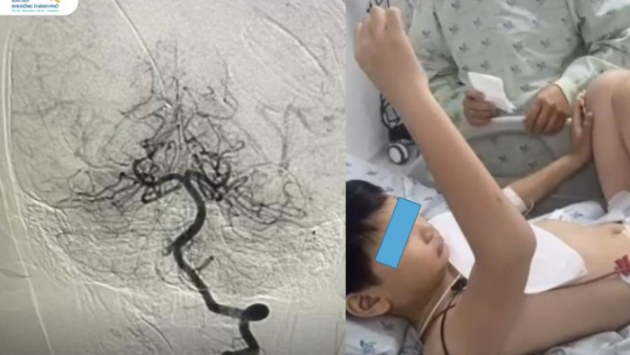

Trẻ đối mặt nguy cơ mắc bệnh từ thói quen hàng ngày

20/03/2026 15:38

Trẻ em và thanh thiếu niên sử dụng thiết bị điện tử nhiều, ngủ không đủ giấc có nguy cơ tăng đường huyết, huyết áp và rối loạn cholesterol, theo nghiên cứu đăng trên tạp chí của...